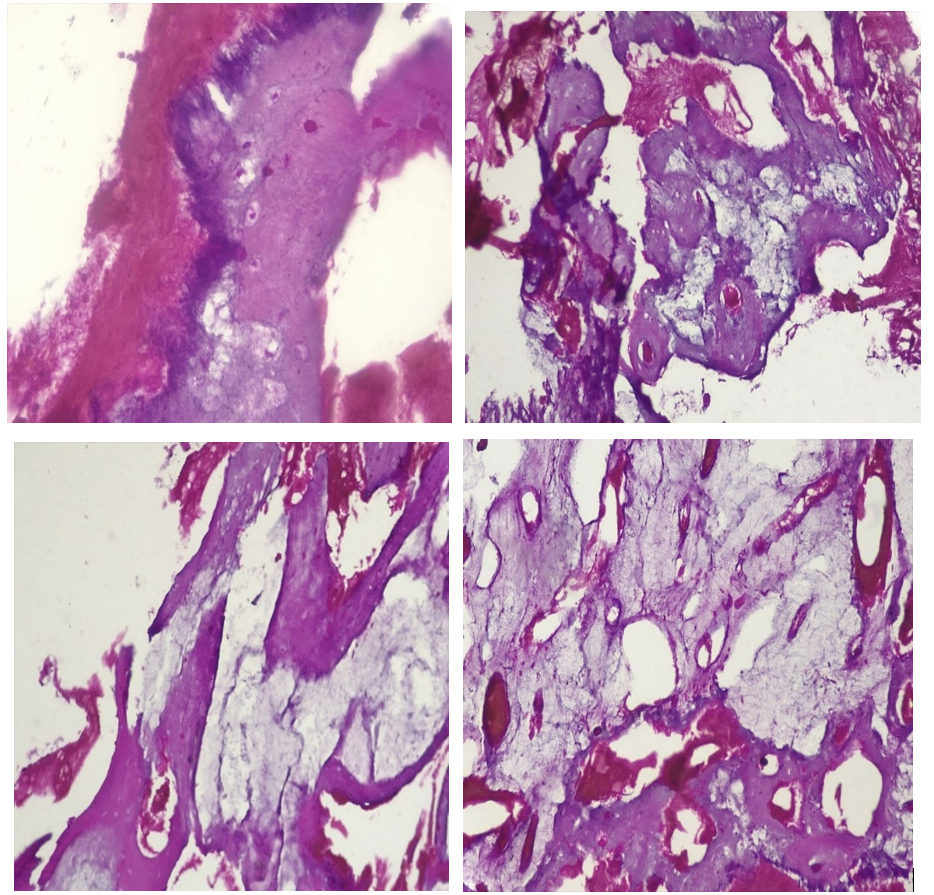

The anatomopathological examination of the bone biopsy (Image 3) revealed fragments of connective tissue, a tumor process made up of areas of atypical chondrocytes, and infiltration of the soft tissue related to the histological appearance of a grade III chondrosarcoma.

Picture 3: The anatomopathological examination of the bone biopsy.